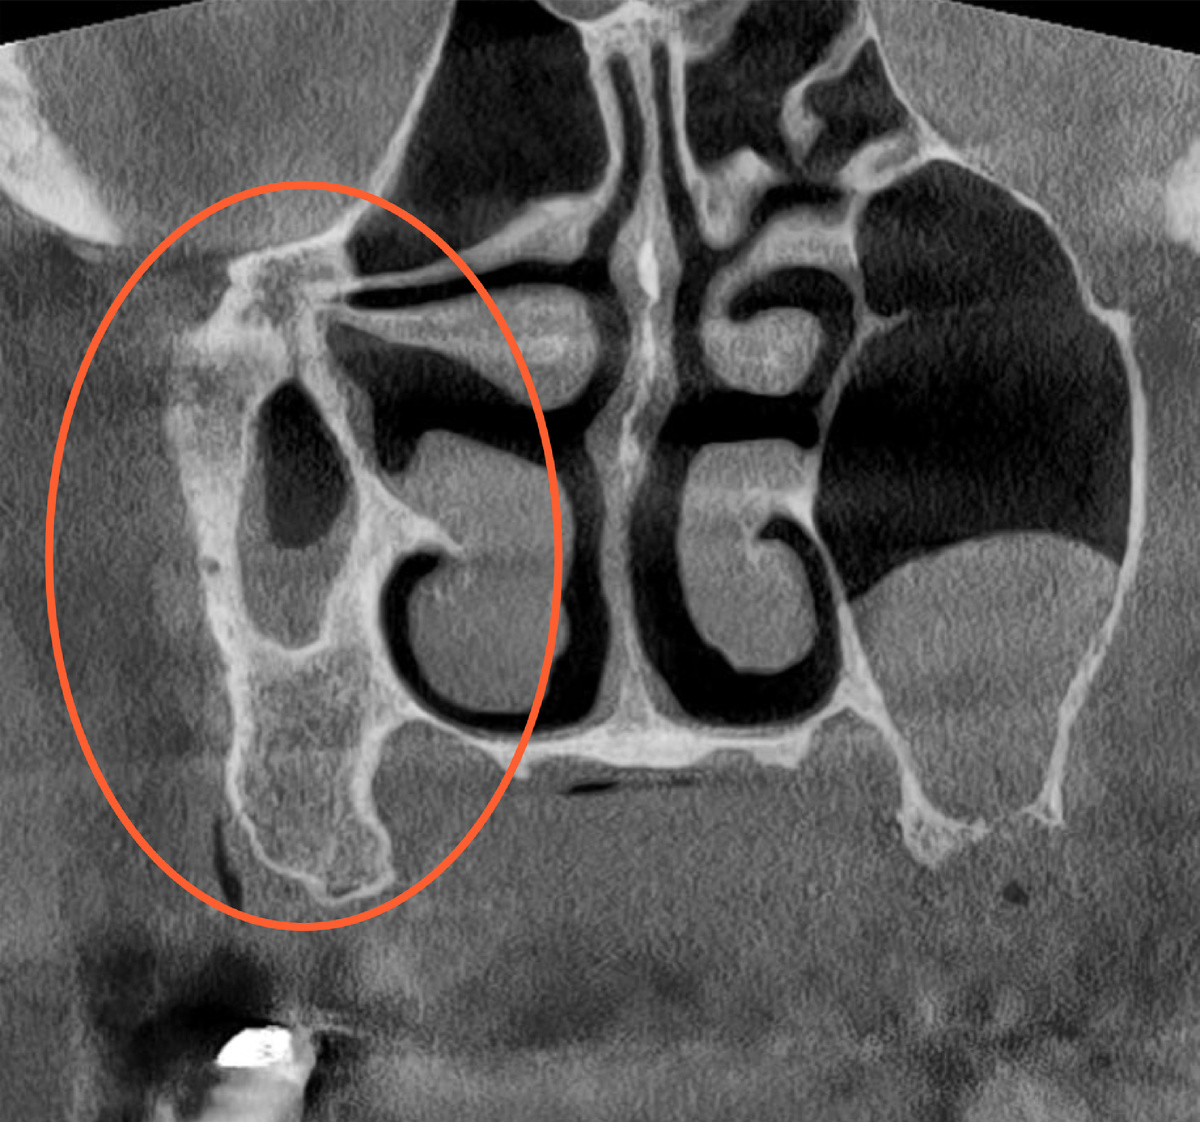

Гипоплазия правого максиллярного синуса. Случайная находка

Данный клинический случай предоставлен опытным врачом-рентгенологом Александром Потаповым👨‍⚕ Гипоплазия правого максиллярного синуса - уменьшение объема (просвета) синуса, уменьшение расстояния между костными стенками. Чаще всего гипоплазия - случайная находка при проведении рентгенологического обследования челюстно-лицевой области. В большинстве случаев течение асимптоматично и не требует вмешательств. На скриншоте панорамного реформата отмечается отсутствие воздушной полости из-за локализации уменьшенной пазухи вне выделенного слоя реформата. Поделитесь в комментариях, с какими случайными находками вы сталкивались в своей практике при проведении рентгенологического обследования пациентов 💻 Узнайте подробнее о программном обеспечении DTX Studio Clinic, оставив заявку на консультацию. ________________

Гипоплазия правого максиллярного синуса - уменьшение объема (просвета) синуса, уменьшение расстояния между костными стенками.

Чаще всего гипоплазия - случайная находка при проведении рентгенологического обследования челюстно-лицевой области.

В большинстве случаев течение асимптоматично и не требует вмешательств.

На скриншоте панорамного реформата отмечается отсутствие воздушной полости из-за локализации уменьшенной пазухи вне выделенного слоя реформата.